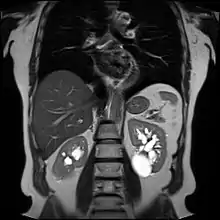

Advanced polycystic kidney disease with multiple cysts.[12]